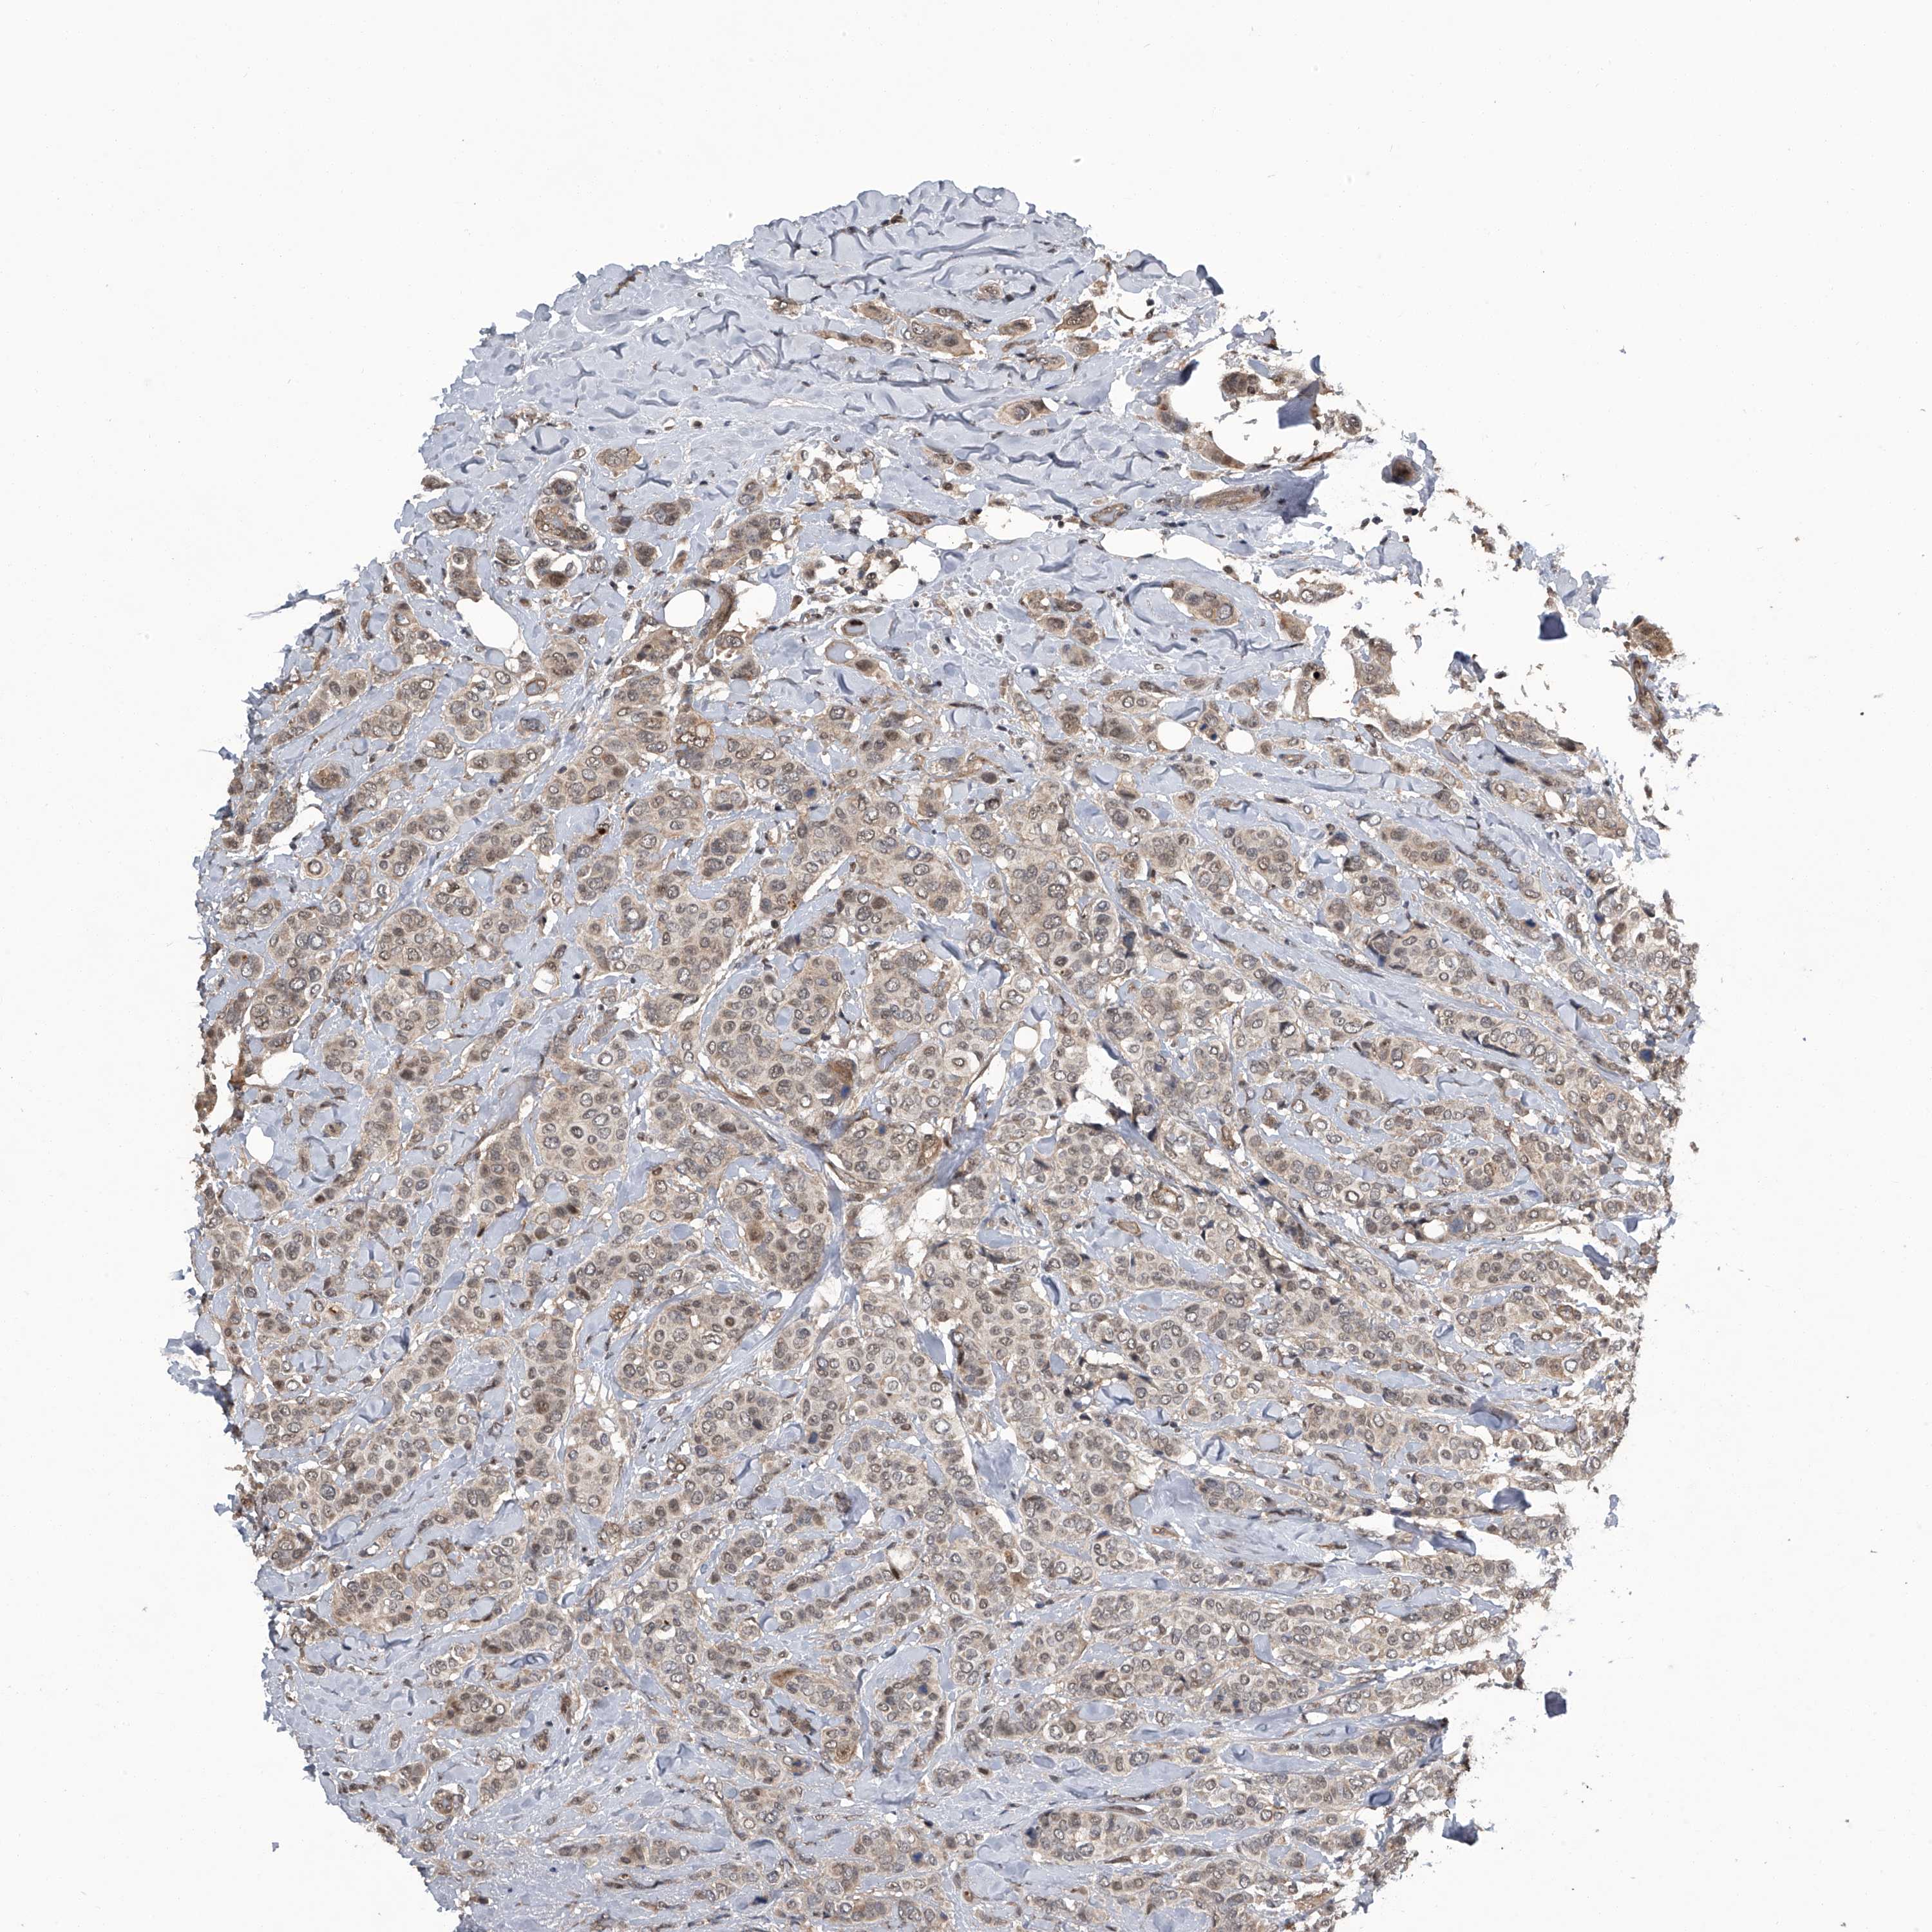

CANCER BREAST CANCER Show tissue menu

BRCA TCGA BRCA VALIDATION PROTEIN EXPRESSION